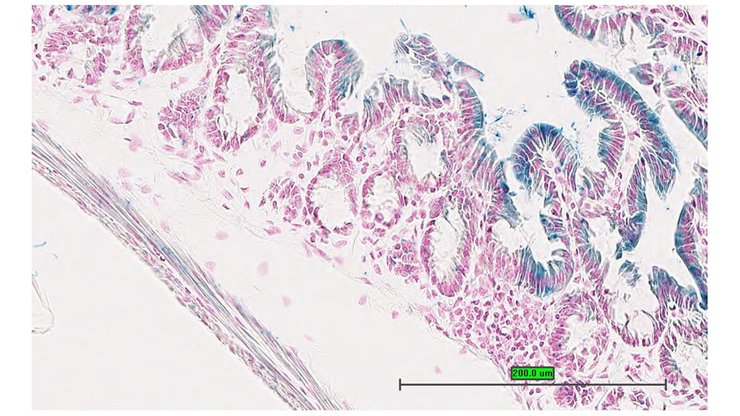

Specimen UC Davis_1870095: postnatal adult; Atf6btm1.1(KOMP)Vlcg/Atf6b+ (more )

Structure Level Pattern Image Note

TS28: jejunum Present UC Davis_1870095

Specimen UC Davis_1870096: postnatal adult; Atf6btm1.1(KOMP)Vlcg/Atf6b+ (more )

TS28: jejunum Present UC Davis_1870096

Specimen UC Davis_1870097: postnatal adult; Atf6btm1.1(KOMP)Vlcg/Atf6b+ (more )

TS28: ileum Present UC Davis_1870097

Specimen UC Davis_1870098: postnatal adult; Atf6btm1.1(KOMP)Vlcg/Atf6b+ (more )

TS28: duodenum Present UC Davis_1870153

Specimen UC Davis_1870154: postnatal adult; Atf6btm1.1(KOMP)Vlcg/Atf6b+ (more )

TS28: jejunum Present UC Davis_1870154

Specimen UC Davis_1870155: postnatal adult; Atf6btm1.1(KOMP)Vlcg/Atf6b+ (more )

TS28: ileum Present UC Davis_1870155